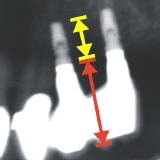

- Fehlerhafte Positionierung der Implantate